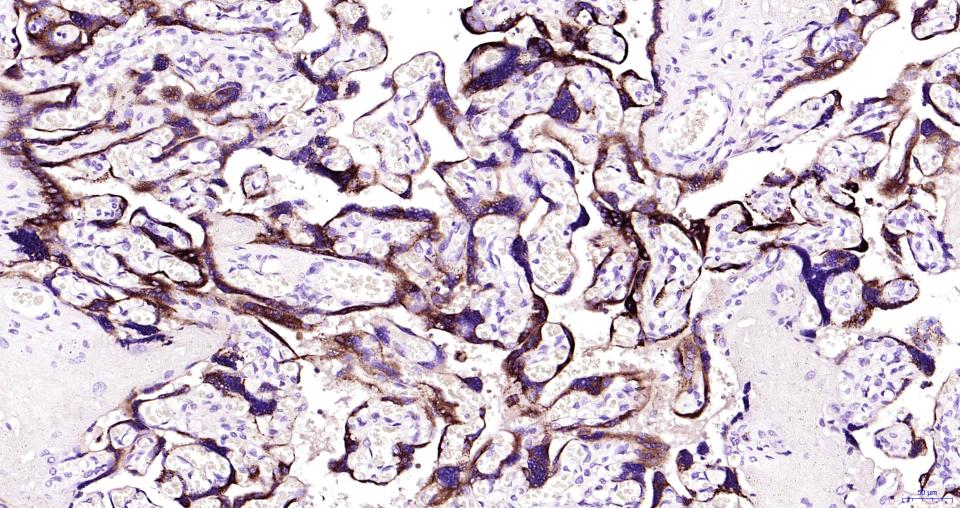

Human CG beta Mouse mAb (bsm-43172M)

產(chǎn)品編號(hào) bsm-43172M

英文名稱(chēng) Human CG beta Mouse mAb

中文名稱(chēng) 人絨毛膜促性腺激素β單克隆抗體

別    名 CGB5; CGB8; CGB3_HUMAN;Choriogonadotropin subunit beta (CG-beta); Chorionic gonadotropin chain beta, Choriogonadotropin subunit beta 3

交叉反應(yīng) Human

產(chǎn)品應(yīng)用 IHC-P=1:100-500,IHC-F=1:100-500,IF=1:100-500

理論分子量 18 kDa

細(xì)胞定位 分泌型蛋白

免 疫 原 Recombinant human Choriogonadotropin subunit beta 3 protein

產(chǎn)品介紹 This gene is a member of the glycoprotein hormone beta chain family and encodes the beta 3 subunit of chorionic gonadotropin (CG). Glycoprotein hormones are heterodimers consisting of a common alpha subunit and an unique beta subunit which confers biological specificity. CG is produced by the trophoblastic cells of the placenta and stimulates the ovaries to synthesize the steroids that are essential for the maintenance of pregnancy. The beta subunit of CG is encoded by 6 genes which are arranged in tandem and inverted pairs on chromosome 19q13.3 and contiguous with the luteinizing hormone beta subunit gene. [provided by RefSeq, Jul 2008]

Expressed in placenta, testis and pituitary.

Paraformaldehyde-fixed, paraffin embedded Human placenta; Antigen retrieval by boiling in sodium citrate buffer (pH6.0) for 15 min; Antibody incubation with Human CG beta Monoclonal Antibody, Unconjugated(bsm-43172M) at 1:200 overnight at 4°C, followed by

(Negative control) Paraformaldehyde-fixed, paraffin embedded Human kidney; Antigen retrieval by boiling in sodium citrate buffer (pH6.0) for 15 min; Antibody incubation with Human CG beta Monoclonal Antibody, Unconjugated(bsm-43172M) at 1:200 overnight at